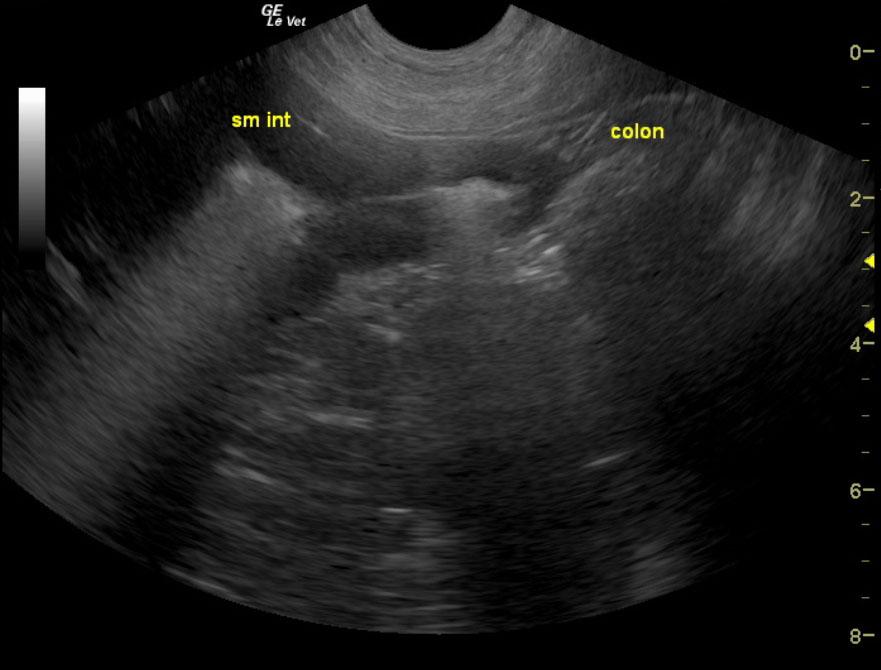

The gastrointestinal tract in this patient presented a distal small intestinal infiltrative mass that measured greater than 12 cm x 3-4 cm wide with loss of mural detail. Some areas of gas penetration within the wall were also noted. Associated lymphadenopathy was present, yet considered minor. This mass appears to be involved in jejunum to ileum and approaches the ileocecocolic region. The only overt suspicion of metastatic disease lies in the 2 x 1 cm mesenteric root lymph node. Other smaller lymph nodes were prominent. However, these may only be inflammatory in nature.

Primary R/O lymphoma. Other round cell neoplasia, carcinoma, and less likely, granulomatous disease. Possible metastasis to mesenteric root lymph node.